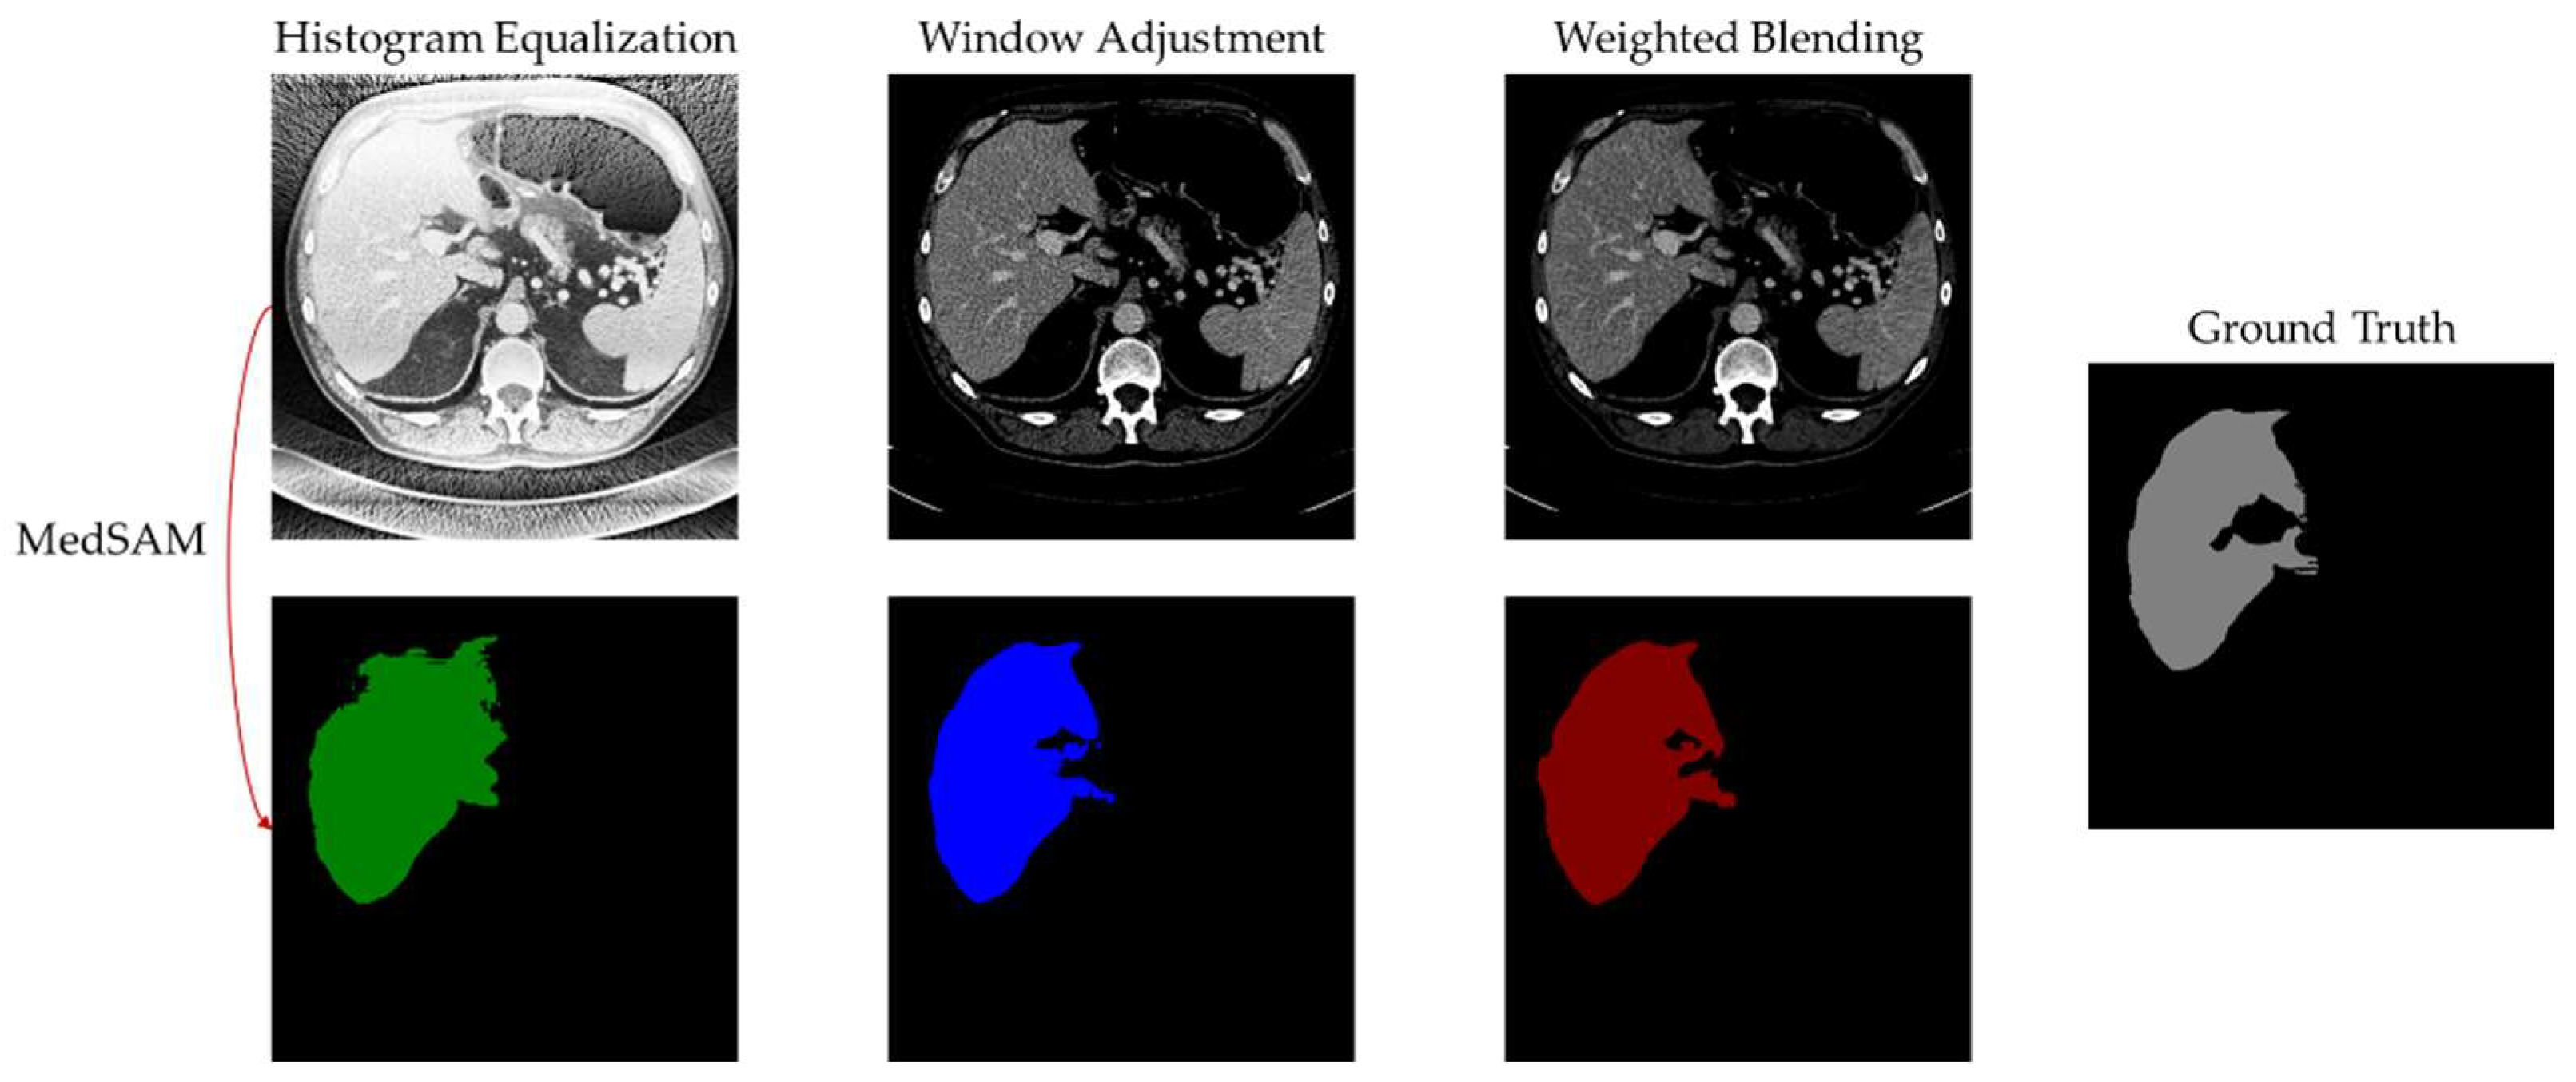

- Digital image enhancement strategies for medical image features: Medical images often contain a high level of noise and details hidden in low-intensity regions. To address this, anisotropic diffusion filters are used for denoising, and histogram equalization is employed to enhance the texture and details of medical images globally. Additionally, the fusion of window level and window width adjustment techniques specific to medical images is applied to target the regions of interest within the image. These strategies aim to achieve global enhancement of medical images while highlighting the desired targets.

4.6. Experimental Results and Analysis

5. Discussion